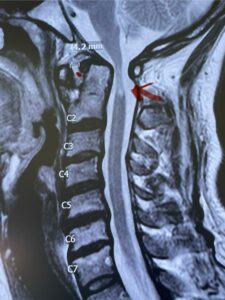

This is a 42 year-old female who presents with severe progressive weakness and numbness and difficulty with balance over a 6-month period. She has a history of having a motor vehicle accident at 5 years old but was never imaged. On exam she was noted to be severely myelopathic. Imaging revealed severe spinal cord compression at the level of C1 (Figs 4a and b).

Fig. 4a: Sagittal T2-weighted cervical MRI demonstrating severe cord compression with myelomalacia of upper cervical spinal cord (red arrow). Notice the increased atlanto-dens interval (red dot).

Fig. 4b: Axial T2-weighted cervical MRI demonstrating severe spinal cord compression from atlanto-axial instability (red arrow)

Cervical x-rays revealed a significantly increased atlanto-axial interval (Fig. 5) On review of her imaging studies it was noted that the right C2 isthmus was very thinned by the vertebral foramen (Figs 6a, b, and c) which would make an attempt at placing a C2 pars screw dangerous. A decision was made to perform an occipital-cervical fusion because only possible unilateral fixation and an extensive C1 laminectomy to be performed eliminating a fixation point if a more traditional C1-C2 was performed. Even if C1 lateral mass screws were able to be placed one could only perform a unilateral screw construct fixation to C2. We performed an occipital cervical fusion down to C4 to get enough inferior fixation and C1 laminectomy. The decompression went well. We placed a left unilateral pars screw and bilateral C3 and C4 lateral mass screws. We placed three 12 mm screws in the midline keel (Fig. 7). Postoperatively the patient had all around improvement in her symptoms and did not qualify for rehab. Her post op films at 6 weeks (Fig. 8)